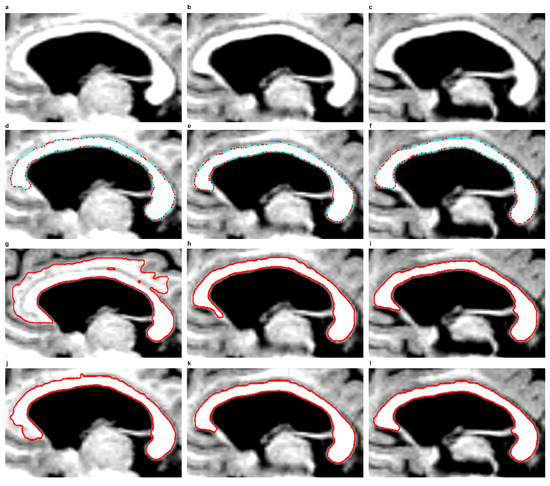

In the EM model, the final contour produced in the previous or next CC slice can also be used for initiation in the next or the previous slice to segment the CC. This is because the EM model, with the defined force F i n f l a t i o n / d e f l a t i o n , can use node motion reversal and thus both shrink and expand at the same time. If the nodes reach the edge searched for, their movement will be damped down. This approach reduces the number of iterations to be completed and simplifies the process of segmenting the CC. This has been shown in examples from Figure 8d–f. In examples from Figure 8d,f, it was enough to complete 20 iterations based on a contour taken from Figure 8e. The use of final contours from previous or subsequent slices for initialisations in the next or previous slices is impossible in the SBGFRLS and DRLSE models. The SBGFRLS model may cause an oversegmentation, as shown in Figure 8g. The DRLSE model, in turn, after an initiation inside the CC cross-section, can only expand, while the surface of the CC can also be smaller in the following slices of MR images.

Figure 8. Corpus callosum segmentation from subsequent example MR images in the sagittal plane, taken from the ’miriad_188_1_MR_1’ set. Row one: ROIs of corpus callosum images taken from three subsequent sagittal planes. Row two: Contours produced by the EM model. Row three: use of the SBGFRLS model. Row four: the DRLSE model. (a) ROI from the first image; (b) ROI from the second image; (c) ROI from the third image; (d) final contour produced based on the contour from item; (e) after 20 iterations were completed; (e) final contour from Figure 7g produced using the initialisation presented in Figure 7f by executing 400 iterations; (f) final contour produced based on the contour from item; (e) after 20 iterations were completed; (gi) final contours produced based on images from items (ac) after completing 550 iterations, with the same initialisation from Figure 7f; (jl) final contours produced based on images from items (ac) after completing 875 iterations, with the same initialisation from Figure 7f.